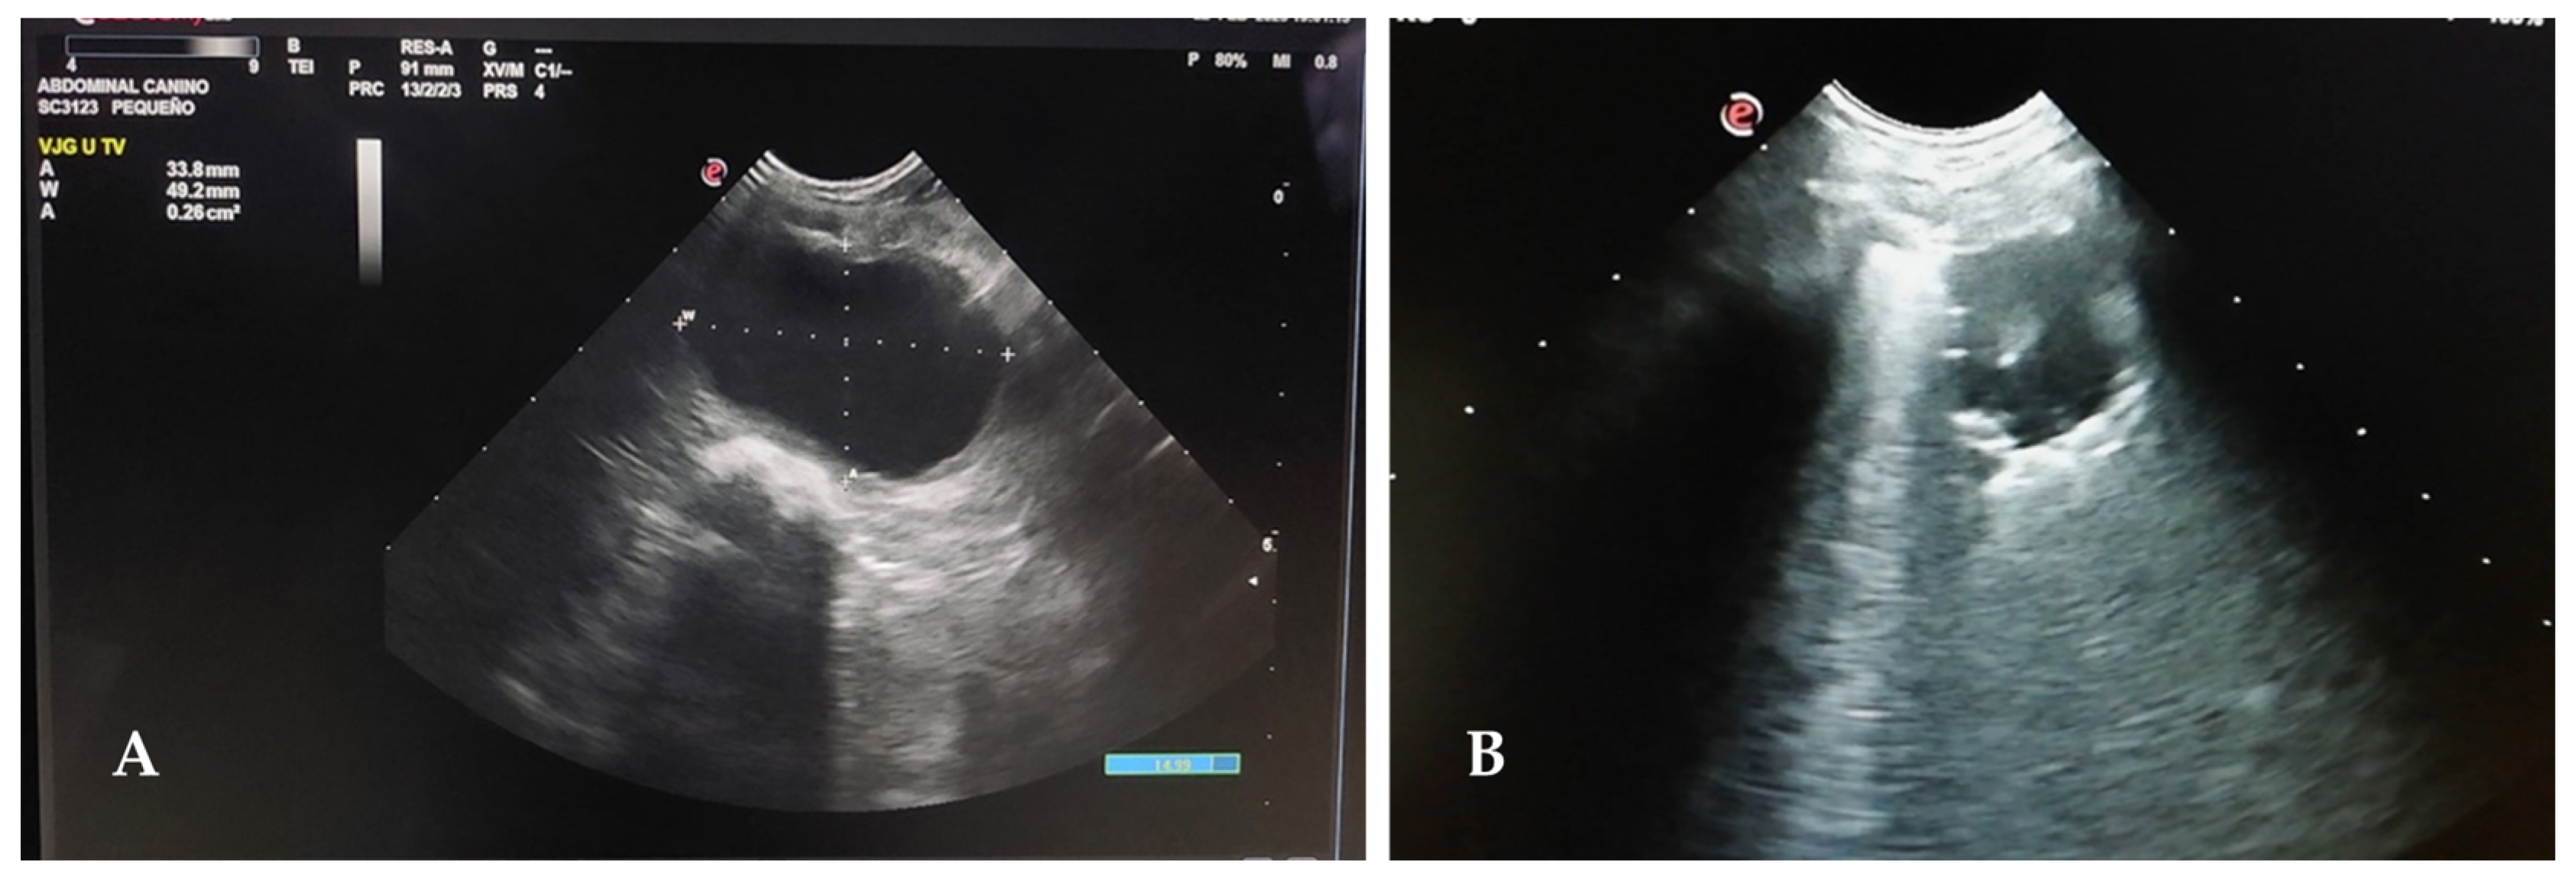

- Boysen, S.; Gommerren, K.; Chalhoub, S. The Esssentials of Veterinary Point of Care Ultrasound: Pleural Space and Lung, 1st ed.; Edra: Zaragoza, Spain, 2022; pp. 111–182. [Google Scholar]